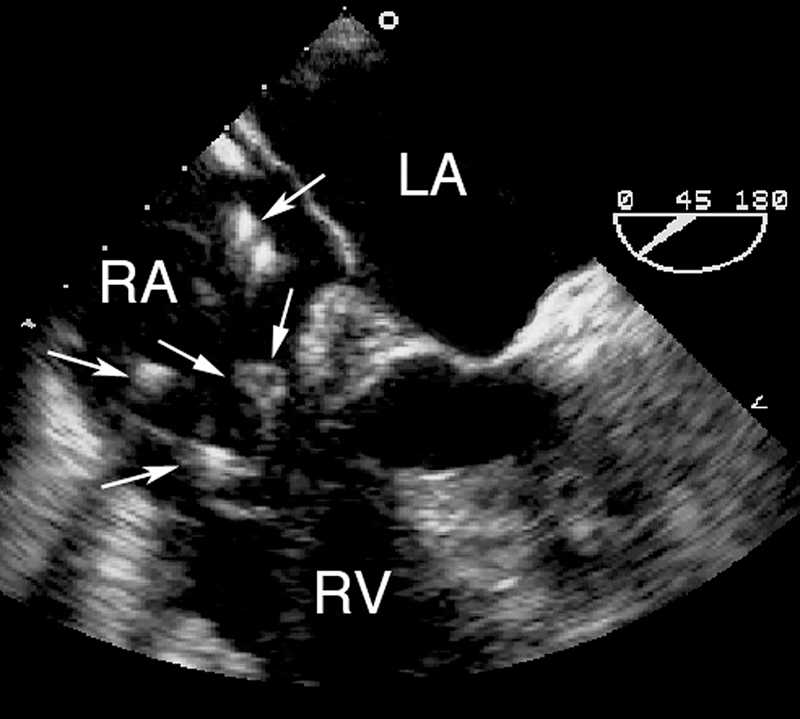

فحوصات تشخيصية لبعض امراض القلب والشرايين التاجية